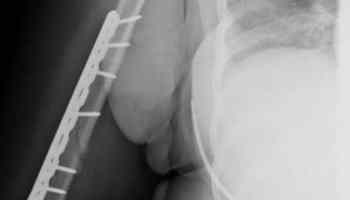

At the hospital, she was told that she fractured her proximal humerus. The proximal humerus is the part of the upper arm bone that is closest to the shoulder. It’s the upper arm bone that is further from the elbow.

At the top of this article is the actual MRI image that showed the break in her arm.

As a result of the serious arm fracture, doctors performed surgery. Surgery increases the full settlement value of a case. She was right hand dominant. The full settlement value of a case is higher if you injured your dominant arm.

In this case, her surgery consisted of having a steel plate with 10 screws inserted into her arm bone.